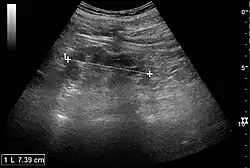

Ultrasound findings that indicate pyelonephritis are enlargement of the kidney, edema in the renal sinus or parenchyma, bleeding, loss of corticomedullary differentiation, abscess formation, or an areas of poor blood flow on doppler ultrasound.[21] However, ultrasound findings are seen in only 20–24% of people with pyelonephritis.[21]

Chronic pyelonephritis with reduced kidney size and focal cortical thinning. Measurement of kidney length on the US image is illustrated by ‘+’ and a dashed line.[20]